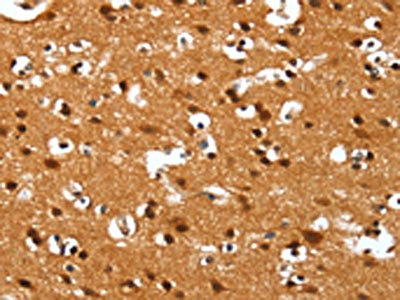

The image on the left is immunohistochemistry of paraffin-embedded Human brain tissue using CSB-PA761300(DEFA4 Antibody) at dilution 1/40, on the right is treated with synthetic peptide. (Original magnification: ×200)